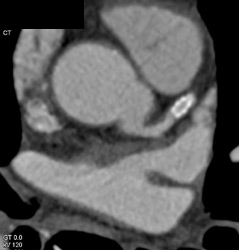

Patent Stent in LAD